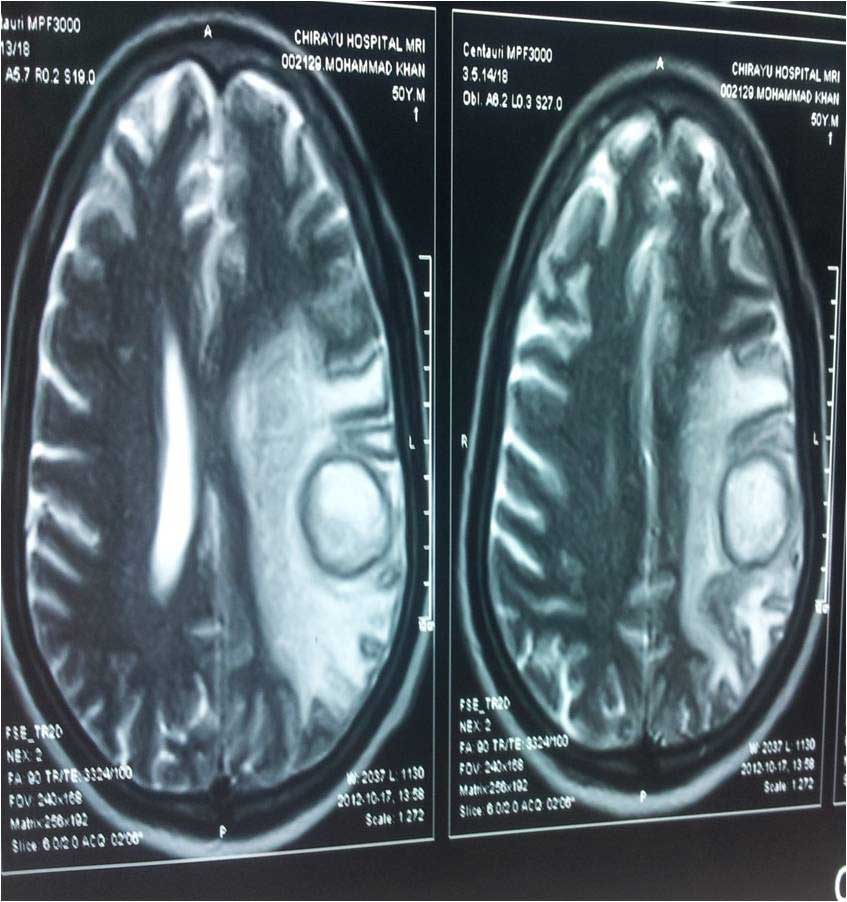

Brain Abscess Brain Abscess Post OP 2 Clinical Intra OP ,After Excising The Granuloma Intaop Scalp Abscess CT Scalp Abscess Cerebellar Abscess Post OP Clinical Cerebellar Abscess Brain TB Granuloma Post OP CT Scan Brain Infection Brain Abscess Preop MRI 2 Brain Abscess PRE OP Clinical 1 Brain Abscess PRE OP Brain Abscess Intraop 2 Brain Abscess Following Shunt Temporal Abscess T2W of TB Granuloma Scalp Abscess Preop CT Marking PRW OP MRI of TB Granuloma Post OP Clinical Photo Post OP Cerebellar Abscess Post OP Brain Abscess Intraop Specimen of Granuloma